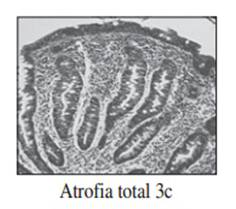

Realizamos una endoscopia digestiva alta y una colonoscopia a la paciente con toma de biopsias, obteniendo el informe de Anatomía patológica.